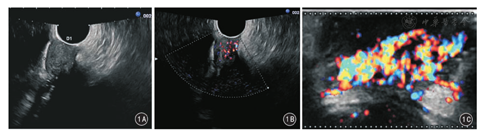

患者女,23岁,2015年1月发现肛周左侧臀部皮下肿物,伴间断胀痛,无发热、恶心、呕吐、腹痛、腹泻等症状,无便血,自以为"痔疮",就诊于当地医院,临床诊断"痔疮合并感染"予以抗感染治疗,肛周疼痛症状缓解,但肿物未见缩小。2015年6月再次出现肛周胀痛,遂二次就诊初诊医院,并以"肛周脓肿、肛瘘"行肛周肿物切除术,术中发现肿物为肛周皮下并累及深部实性软组织肿瘤,未予切除,建议至上级医院进一步治疗。2015年6月16日,患者就诊于山西省肿瘤医院,以"肛周肿物"收住院。患者自发病以来精神、食欲、睡眠可,大、小便正常,无明显消瘦。入院后行血常规、尿常规、凝血5项、肝肾功能、乙肝系列、人类免疫缺陷病毒等实验室检查,结果均无异常。经直肠超声检查提示肛门左侧皮肤及皮下软组织内实性不均质低回声病变,形态欠规则,边界较清,见低回声纤维包膜;彩色多普勒血流显像(color Doppler flow imaging, CDFI)检测见丰富血流信号(图1)。MRI提示:肛门左侧皮肤及皮下深部软组织内见软组织信号影,范围约5.3 cm×4.1 cm ×4.0 cm,信号不均匀,T1WI与肌肉呈等信号,T2WI呈中、高混杂信号,病变内见点状、小灶状低信号区,DWI呈不均匀等信号,注射对比剂钆喷酸葡胺注射液增强扫描呈明显强化,强化区域似呈条带状、旋涡状强化,病变内点状及灶状低信号区未见强化(图2)。患者于2015年6月22日在全身麻醉下行臀部肛周肿物切除术。术中见肿物位于肛门左后方3 cm处,皮肤表面可触及的肿瘤直径约4 cm,色白、质硬。沿肿物边缘切开皮肤,仔细分离肿物与周围组织粘连,避免损伤肛门括约肌及直肠,完整游离肿物,切除标本送病理检查。大体标本见:附皮肤软组织一块,大小6 cm×5 cm×4 cm,皮肤大小5.5 cm×4.5 cm;皮肤表面可见一隆起,范围4.5 cm×4 cm,肿物切面灰白、质韧。术后病理检查提示:镜下瘤细胞呈梭形,围绕血管呈束状、结节状排列;免疫组织化学检测:AE1/AE3阴性,Vimentin阳性,S-100阴性,平滑肌肌动蛋白阳性,CD34阳性,Ki67约2%,β-catenin阳性。病理诊断:血管平滑肌瘤(图3、图4)。

超声检查是诊断此类病变的常用方法。CAL的超声声像图表现为圆形、椭圆形、边界清晰的不均质低回声肿块,可见包膜回声,包膜主要为纤维性假包膜。超声声像图的回声高低与病变内部的病理改变有关。本例患者超声检查肿瘤内部呈均匀的低回声,与病灶内部的平滑肌纤维细胞及平滑肌束排列规整、界面少相关。CDFI显示肿瘤血流信号丰富,与肿瘤内部血管数目相应较多、管腔内径较大、流速快及血流丰富有关。CDFI对CAL诊断具有特殊重要意义。CDFI的血流信号强度与CAL血流分级及病理类型相关[10,11],丰富的彩色血流信号以Alder Ⅲ级者多见[10,11,12]。超声引导穿刺活检术可以明确诊断CAL,适用于部分术前不能确定诊断或无法鉴别良恶性肿瘤的患者[10]。